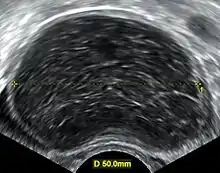

Transvaginal ultrasonography of a hemorrhagic ovarian cyst, probably originating from a corpus luteum cyst. The coagulating blood gives the content a cobweb-like appearance.

Transvaginal ultrasonography of a hemorrhagic ovarian cyst, probably originating from a corpus luteum cyst. The coagulating blood gives the content a cobweb-like appearance.

Ovarian cysts are usually diagnosed by ultrasound, CT scan, or MRI, and correlated with clinical presentation and endocrinologic tests as appropriate.[10]

Ultrasound

Follow-up imaging in women of reproductive age for incidentally discovered simple cysts on ultrasound is not needed until 5 cm, as these are usually normal ovarian follicles. Simple cysts 5 to 7 cm in premenopausal females should be followed yearly. Simple cysts larger than 7 cm require further imaging with MRI or surgical assessment. Because they are large, they cannot be reliably assessed by ultrasound alone; it can be difficult to see posterior wall soft tissue nodularity or thickened septation due to limited ultrasound beam penetrance at this size and depth. For the corpus luteum, a dominant ovulating follicle that typically appears as a cyst with circumferentially thickened walls and crenulated inner margins, follow up is not needed if the cyst is less than 3 cm in diameter. In postmenopausal patients, any simple cyst greater than 1 cm but less than 7 cm needs yearly follow-up, while those greater than 7 cm need MRI or surgical evaluation, similar to reproductive age females.[11]